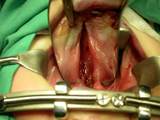

Las técnicas quirúrgicas que aplicamos a los niños fisurados son las más avanzadas y aceptadas internacionalmente, con resultados de alta calidad. En su primer mes de vida y sólamente sí lo precisa, le colocamos en su boquita ORTOPEDIA PREQUIRÚRGICA. A los 3 meses operamos el labio, la nariz y la encía. A los 12 meses se interviene la fisura palatina. Al año el niño está definitivamente corregido.

El tratamiento de los niños con fisura facial debe ser integral y realizado por un equipo multidisciplinar, para así obtener los mejores resultados funcionales y estéticos.